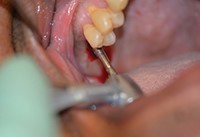

هنگامی که بیهوشی عمیق با نفوذ سپتوکائین (سپتودونت) (با 1:100،000 اپینفرین) در هر دو ناحیه گونه و دهان انجام شد، یک تیغ گرد شماره ی 8 به منظور نفوذ بافت کراتینیزه شده و ایجاد شکاف در استخوان تاج مورد استفاده قرار گرفت. بعد، یک مته با قطر 1.8 میلی متری با آبیاری زیاد، برای ایجاد یک استئوتومی که بدون نفوذ انترال کف سینوس را گسترش می دهد (شکل 3) استفاده شد.

به دنبال پروتکل تجویز شده، یک پانچ بافت هدایت کننده 6.0 میلیمتری برای حذف بافت توپی متمرکز در اطراف سوراخ آزمایشی اولیه مورد استفاده قرار گرفت (شکل 4). اکنون که استخوان تاج در معرض قرار گرفته است، ابتدا استوئتومی بالایی 3.5 میلیمتری (شکل 5)، و سپس استوئتومی گسترده ی 5.7 میلی متری (شکل 6) استفاده شد. به طور معمول، با سیستم OCO، پروتکل اجازه ی پیشرفت از مرحله آزمایشی به قطر نهایی را در یک مرحله به دلیل طراحی منحصر به فرد مته می دهد.

شکل 3. مته حفاری 1.8 میلی متری با نقطه توقف عمق 6.0 میلیمتری در محل.

شکل 4. یک پانچ بافتی هدایت کننده ی 6.0 میلیمتری.